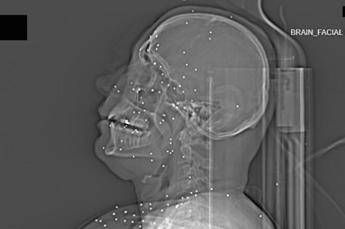

(Adnkronos) – Il Guardian, quotidiano britannico da anni impegnato nel documentare violazioni dei diritti umani, ha pubblicato un’inchiesta che aggiunge un tassello crudo e difficilmente contestabile alla comprensione della repressione delle proteste in Iran. Non si tratta di testimonianze verbali, non di racconti filtrati dalla distanza o dalla propaganda, ma di immagini mediche: radiografie e Tac. Fotografie in scala di grigi che mostrano, letteralmente, la violenza impressa nei corpi. Il volto di Anahita – nome di fantasia, poco più che ventenne – appare come un cielo notturno attraversato da punti luminosi. Piccole sfere metalliche, da 2 a 5 millimetri, disseminate sul viso, nelle orbite oculari, persino nella massa scura del cervello. Sono proiettili “birdshot”, pallini da caccia sparati da un fucile a pompa. A distanza ravvicinata, spiegano gli esperti, non sono affatto “meno letali”: possono frantumare ossa, devastare tessuti molli, perforare facilmente un bulbo oculare. Anahita ha perso almeno un occhio, forse entrambi. Quell’immagine non è un caso isolato. Fa parte di oltre 75 set di esami diagnostici provenienti da un singolo ospedale di una grande città iraniana, raccolti nel corso di una sola serata, durante la stretta repressiva di gennaio. Una concentrazione temporale che, già di per sé, racconta una dinamica da “mass casualty”, evento con numerose vittime simultanee, tipico degli scenari di guerra o dei grandi disastri. Le scansioni mostrano ferite che i medici definiscono “catastrofiche”. Vahid – altro nome modificato – presenta un proiettile di grosso calibro conficcato nel collo. La trachea è spinta lateralmente, il sangue si accumula, i tessuti gonfi e danneggiati comprimono le strutture vitali. In un altro caso, un uomo di mezza età ha un proiettile sospeso nel cervello, accompagnato da una bolla di gas intracranica: segno di trauma devastante, al quale verosimilmente non si può sopravvivere. Due giovani uomini mostrano pallottole ad alto calibro alloggiate accanto alla colonna vertebrale. Una giovane donna presenta un proiettile deformato che sembra aver attraversato la gabbia toracica, lesionato il polmone e arrestato la sua corsa vicino alla spina dorsale. Le valutazioni, condotte congiuntamente dal Guardian e dalla piattaforma di fact-checking Factnameh, sono state affidate a un panel indipendente di specialisti internazionali: medici d’urgenza, radiologi, esperti di trauma imaging e balistica. Un ex medico iraniano di pronto soccorso, anch’egli consultato, ha confermato la coerenza del software utilizzato per gli esami e l’assenza di segni di manomissione. Gli esperti precisano che, senza cartelle cliniche complete, non è possibile formulare diagnosi definitive sui singoli pazienti. Ma il quadro complessivo, spiegano, è inequivocabile. “Se spari con armi di quel tipo contro delle persone, stai cercando di ucciderle.” La frase di uno degli specialisti di imaging traumatico riassume la sostanza tecnica dell’inchiesta. Le immagini mostrano proiettili full metal jacket, tipicamente utilizzati nei fucili d’assalto come AK-47 o KL-133, armi in dotazione ai Pasdaran, il Corpo delle guardie rivoluzionarie islamiche (IRGC). Non strumenti di controllo della folla, ma armamenti progettati per la guerra. Accanto ai colpi di grosso calibro, emerge con forza un altro elemento: l’uso sistematico dei pallini metallici. L’Iran è tra i pochi Paesi in cui le forze di sicurezza impiegano birdshot metallico. A lunga distanza, i pallini si disperdono e colpiscono indiscriminatamente. A distanza ravvicinata, diventano devastanti: decine, talvolta centinaia di micro-proiettili che penetrano simultaneamente nei tessuti. Le radiografie raccontano questa brutalità in modo quasi didascalico. Il torace di Ali – anche qui, nome di fantasia – contiene oltre 174 pallini metallici concentrati nella cavità destra. Il polmone parzialmente collassato, circondato da sangue e gas. Secondo gli esperti consultati, anche con un intervento chirurgico immediato e massiccio, il rischio di morte rimane altissimo. “Molti pensano che i pallini siano meno letali dei proiettili veri. Non è così,” spiega Rohini Haar, medico d’urgenza e consulente di Physicians for Human Rights. “A distanza ravvicinata, quelle sfere metalliche sono come cento piccoli proiettili.” Ma non è solo la gravità delle ferite a colpire. Caso dopo caso, le immagini mostrano corpi colpiti al volto, al torace, ai genitali. Ventinove pazienti risultano feriti al viso da birdshot. Almeno nove presentano lesioni nell’area genitale o pelvica, provocate sia da pallini sia, in alcuni casi, da fucili ad alto calibro. Una donna di mezza età ha quasi 200 pallini distribuiti tra cosce e pelvi. Un uomo di 35 anni mostra ferite analoghe. Le conseguenze cliniche, secondo le analisi mediche, includono sfigurazioni gravi, danni permanenti agli organi genitali, possibili esiti a lungo termine come incontinenza, sterilità, impotenza. Colpire gli occhi. Colpire il torace. Colpire i genitali. Non una casualità balistica, ma una tendenza che diversi medici iraniani descrivono come ricorrente. Ahmad – identità verificata dal Guardian – riferisce le parole di un collega chirurgo oculista: decine di interventi per rimuovere occhi irreparabilmente danneggiati, inclusi quelli di adolescenti. Il paziente più giovane, racconta, era una ragazza di 14 anni. Portata in ospedale dai genitori e dal fratello. Colpita direttamente all’occhio sinistro mentre la famiglia si trovava a una manifestazione. Le forze di sicurezza, secondo il racconto, sparavano dal tetto di un edificio civile. Il danno era tale che il bulbo oculare non ha potuto essere salvato. Ahmad parla di uno schema che “suggerisce fortemente un intento di causare disabilità permanenti piuttosto che danni accidentali”. Lesioni agli occhi, al cuore, meno frequentemente ai genitali. Organi vitali e parti del corpo simbolicamente cariche, la cui distruzione produce non solo sofferenza fisica, ma devastazione psicologica e sociale. Un altro medico, anch’egli verificato, descrive una casistica che attraversa tutte le età: “dai nonni ai bambini piccoli”. Ferite da pistole, da AK-47, da fucili a pompa. Tra i pazienti anziani, una donna di circa 65 anni, colpita a distanza ravvicinata mentre cercava di recuperare la nipote. I tentativi di rianimazione non sono bastati. “Sto ancora cercando di farci i conti,” confessa il medico. “Puoi sopportare solo fino a un certo punto.” Le immagini analizzate rappresentano, sottolineano gli esperti, solo una frazione del totale. In situazioni con numerosi feriti, gli ospedali sono costretti a triage severi. Le scansioni CT vengono riservate ai casi ritenuti salvabili. Molti colpiti alla testa con armi ad alto calibro, osservano i medici, “non arrivano nemmeno alla TAC”. È proprio questo aspetto a rendere l’inchiesta ancora più inquietante. Le radiografie non mostrano l’intera dimensione della violenza, ma soltanto il segmento dei sopravvissuti immediati. Coloro che, nonostante ferite devastanti, sono arrivati vivi abbastanza da essere sottoposti a esami diagnostici. Nel loro insieme, queste immagini compongono un racconto visivo che travalica la retorica politica. Sono prove cliniche di una repressione che, secondo i medici consultati, presenta caratteristiche più vicine a un conflitto armato che a operazioni di ordine pubblico. In assenza di osservatori internazionali sul campo, la medicina diventa archivio involontario della storia. Ogni pallino visibile in una radiografia, ogni proiettile incastonato in una vertebra o in un cranio, non è soltanto un dato clinico. È la traccia materiale di una scelta: quella di usare armi da guerra contro civili, manifestanti, passanti.